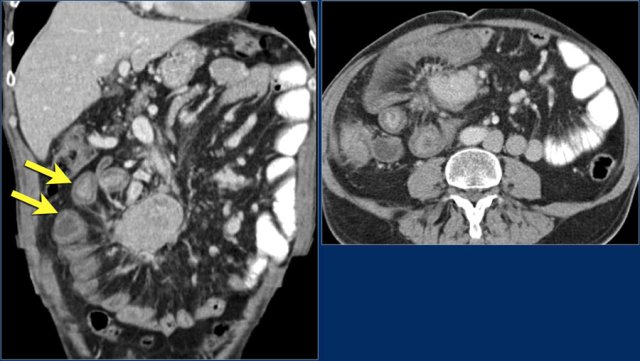

Here another adenocarcinoma located in the jejunum.

There are multiple lymph nodes (red arrow) and there is fat stranding (yellow arrows).

It should not be mistaken for mesenteric panniculitis as these large necrotic lymph nodes are pathologic.